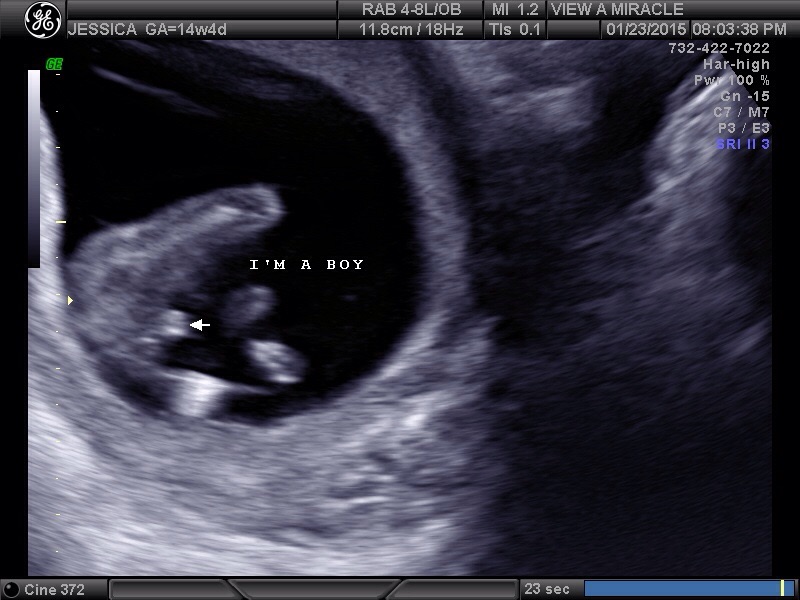

• I went to a place for elective ultrasound and we found out our first is a little boy ! Thomas Xavier. I found out at 14 wk 5 d